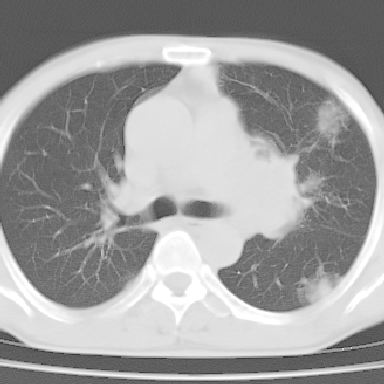

以下是引用zjzjr在2007-3-23 17:24:00的发言:[br]双侧肺门淋巴结明显肿大,以左侧为著,支气管受压变窄,肺内可见结节状及絮状高密度影,边缘模糊.考虑淋巴瘤肺内浸润.